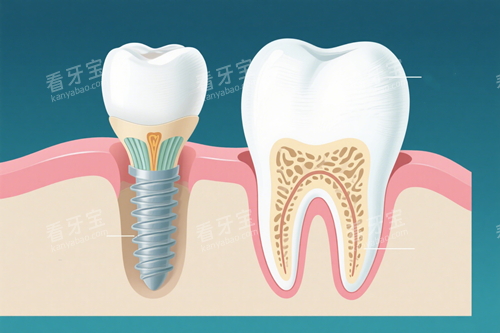

ЦЦЦІСАЧчОҒПЦөъСАүЖРЮёөµДёЯ¶ЛәәКхӘ¬ТФЖдОИ№МДНУГҰұҢУҢьЧФИ»САµДМШРФЙоКЬ»әХЯПІ°®ҰӘ